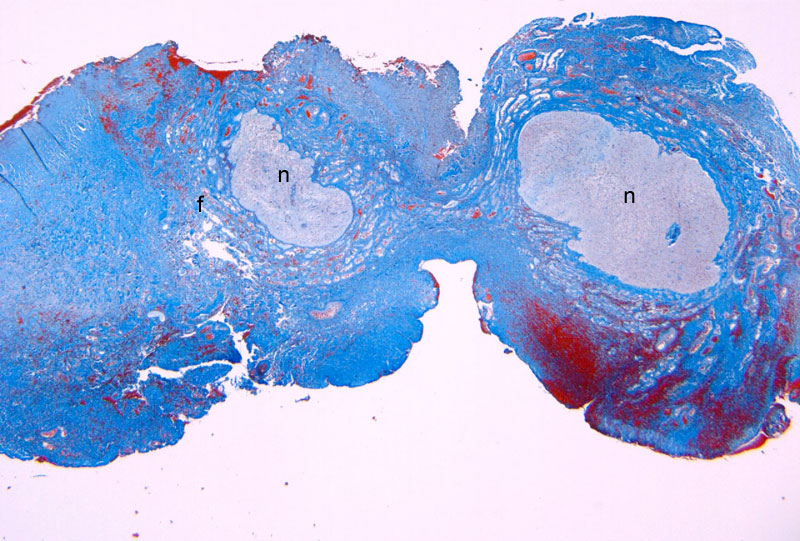

Hematoxylin & eosin

Trichrome stain: This specimen is taken from a different case and stained with trichrome stain. Note that the neural parenchymal islands (n) and the surround fibroconnective tissue (f) are well demonstrated. Trichrome typicall demonstrate the difference in color between these two element nicely. Note that similar to our case, there is also a rich vascular network around these parecnymal islands (v).